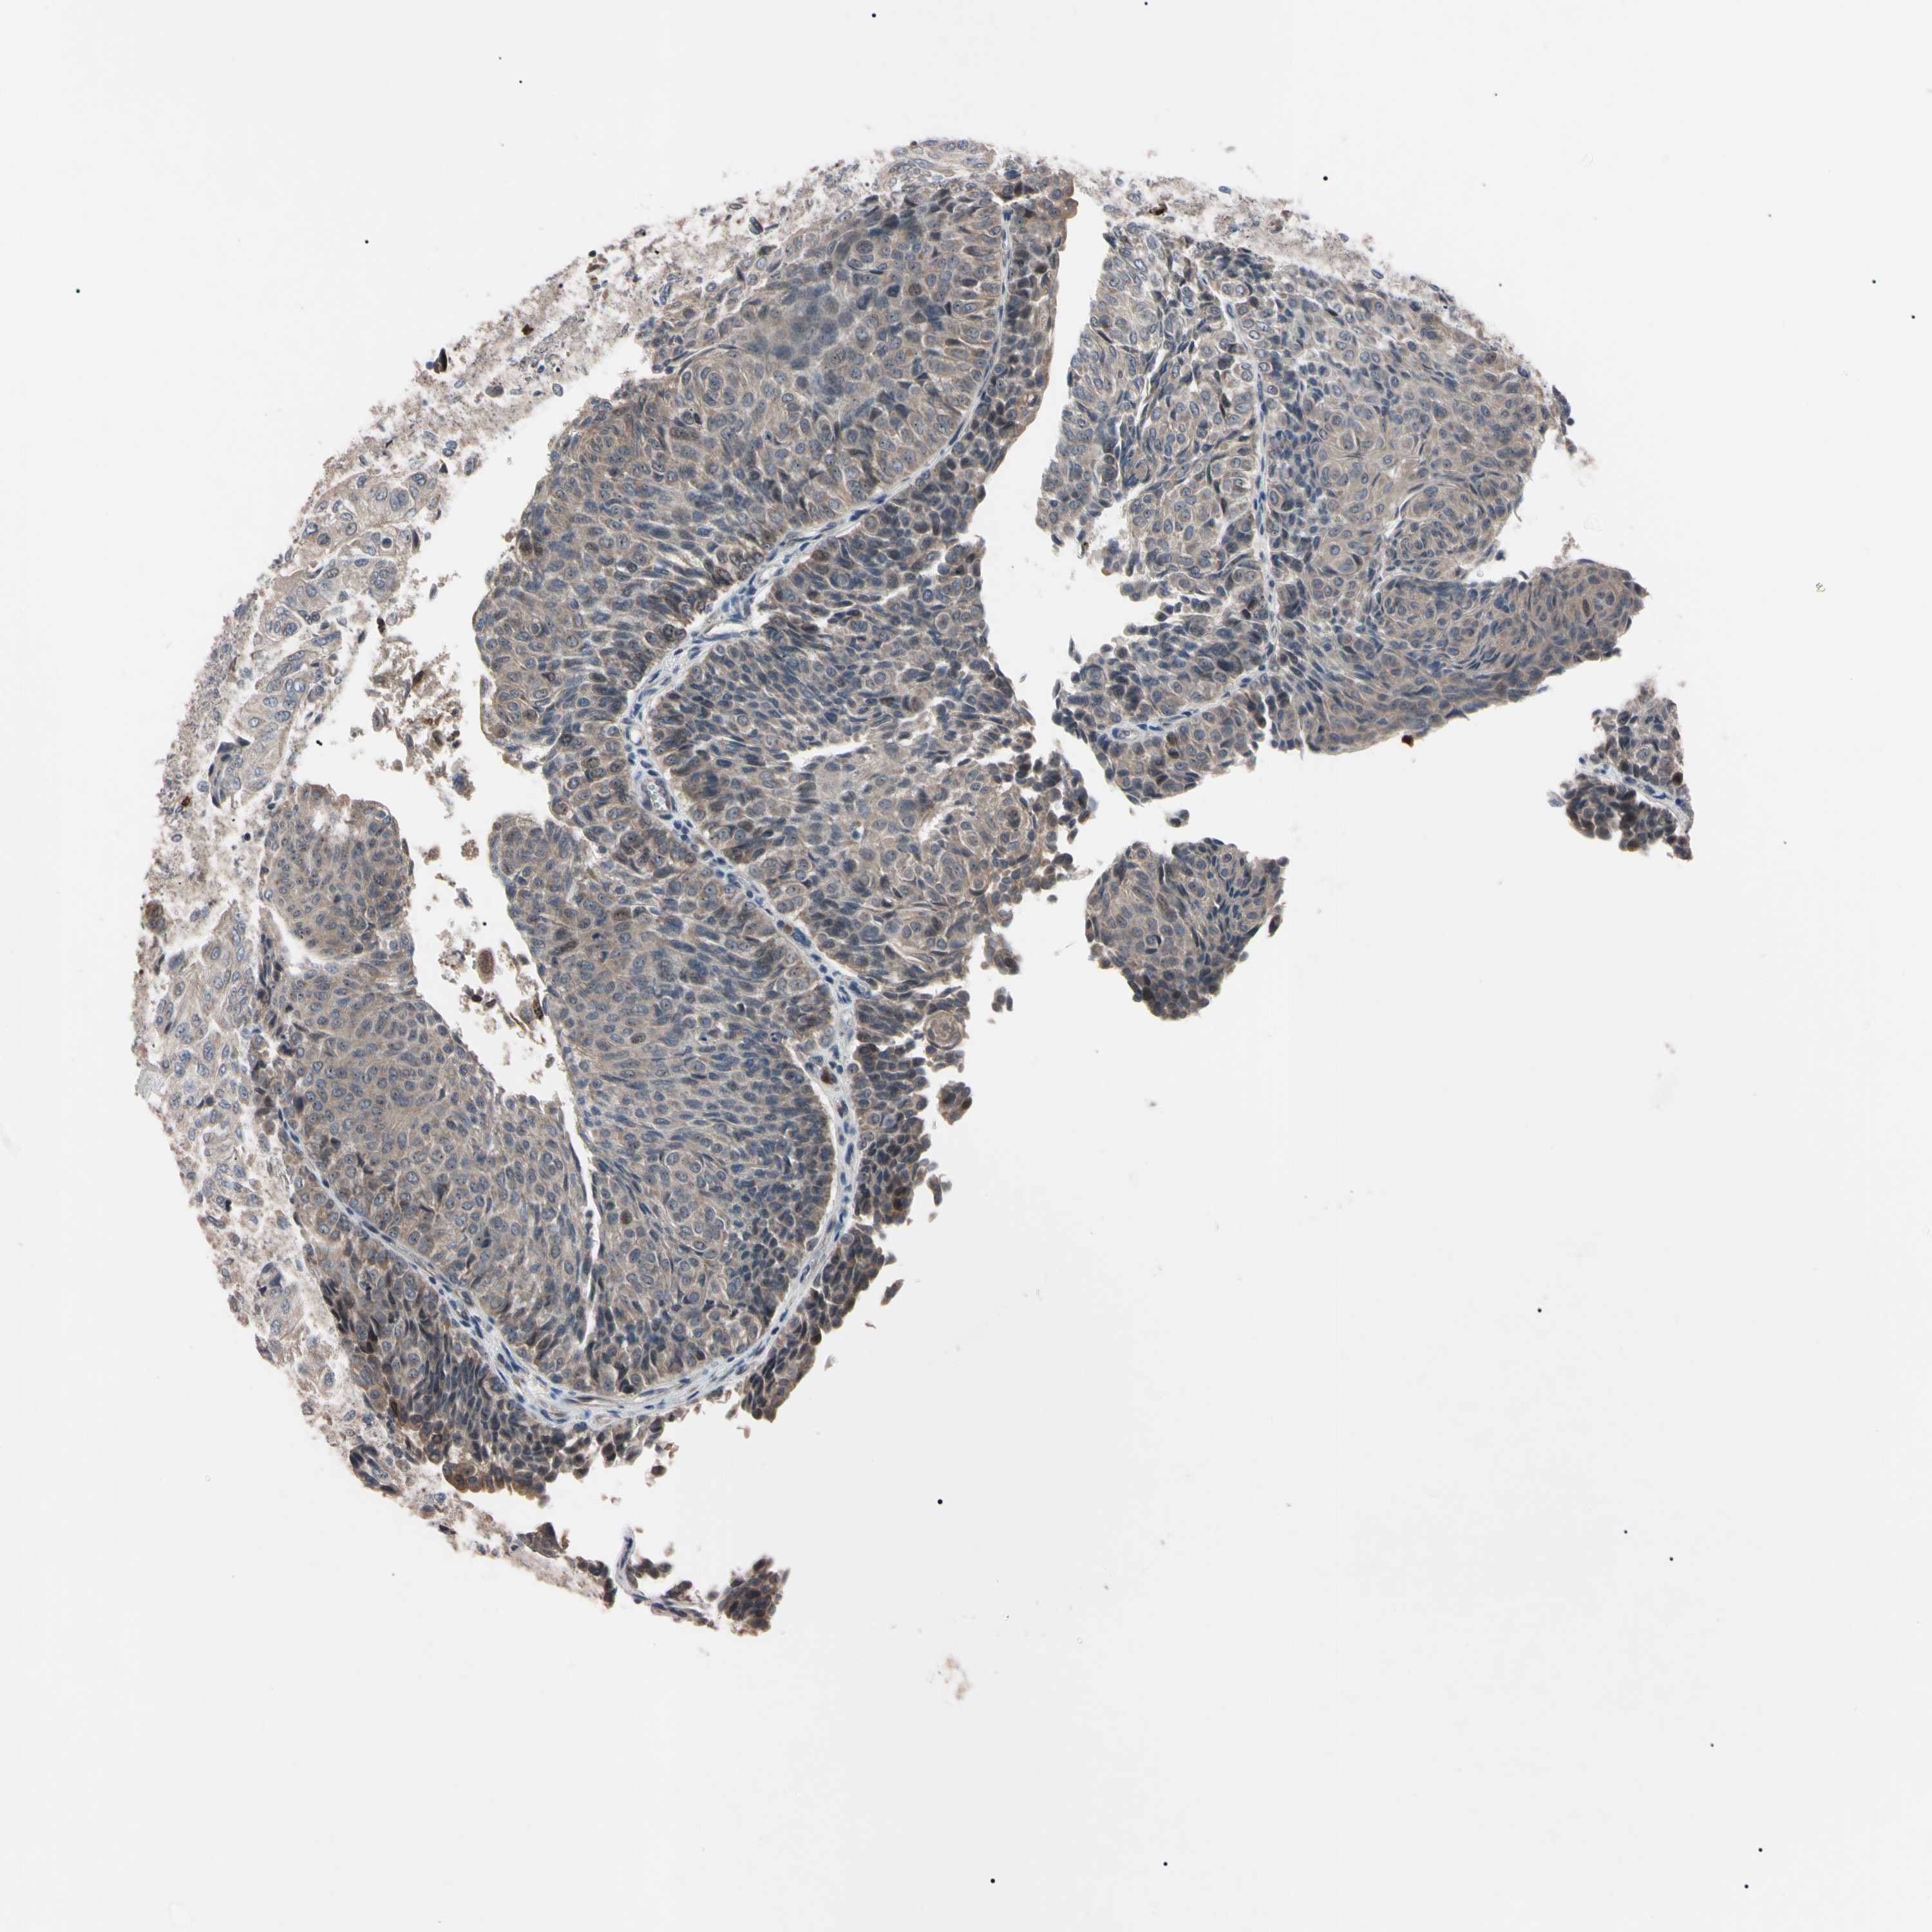

UROTHELIAL CANCER - Protein expressioni

A mouse-over function shows sample information and annotation data. Click on an image to view it in a full screen mode. Samples can be filtered based on level of antibody staining by selecting one or several of the following categories: high, medium, low and not detected. The assay and annotation is described here.

Note that samples used for immunohistochemistry by the Human Protein Atlas do not correspond to samples in the TCGA dataset.

Antibody stainingi

Antibody staining in the annotated cell types in the current human tissue is reported as not detected, low, medium, or high, based on conventional immunohistochemistry profiling in selected tissues. This score is based on the combination of the staining intensity and fraction of stained cells.

Each image is clickable and will lead to virtual microscopy that enables deeper exploration of all samples and also displays staining intensity scores, fraction scores and subcellular localization as well as patient and tissue information for each sample.

Antibody HPA008052

Antibody CAB010277

Urothelial carcinoma, Low grade

Urothelial carcinoma, High grade